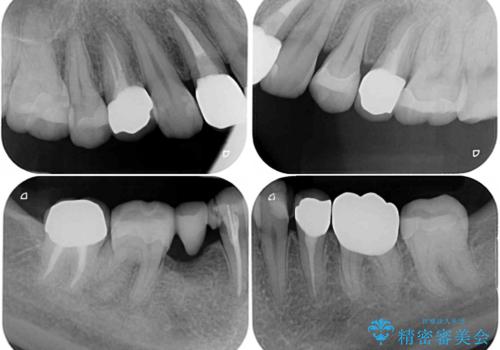

以前はセラミッククラウンのフレームとして金属が使用されており、歯肉の経年変化やセラミックのすり減りなどにより、金属が見えるようになってくることがあります。

現在は金属の代わりに強化セラミックを使用したオールセラミッククラウンが主流です。金属色が気になる方はご相談ください。